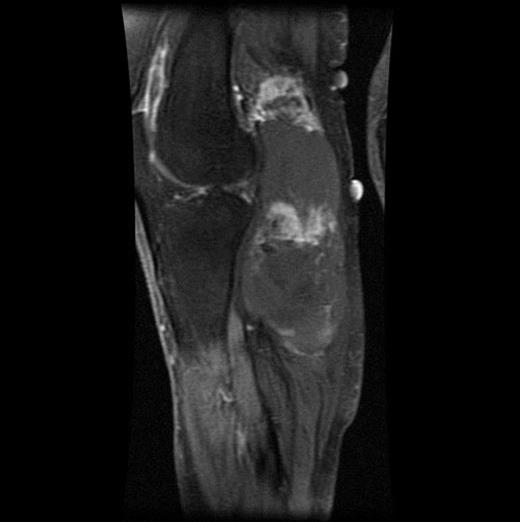

The MRI scan of the right knee (Figs 2 and 3) with gadolinium-enhancement showed a large mass lesion in the posterior aspect of the right knee extending into the popliteal fossa and into the upper third of the right leg having appearance of bursal pathology. Post gadolinium images showed evidence of circumferential rim enhancement but no internal enhancement indicating the presence of a fluid filled lesion. The mass (Figs 4 and 5) measured ∼8.39 × 6.14 × 12.72 cm and was seen between semimembranosus and biceps femoris muscles. There was no evidence of any infiltration of either the sciatic nerve or the popliteal vessels. A likely diagnosis of complicated synovial cyst with a differential diagnosis of haematoma was reported and a provisional diagnosis of Baker's cyst was established.

T1-weighted MRI image showing mass occupying whole of posterior aspect of knee extending to proximal portion of the leg.